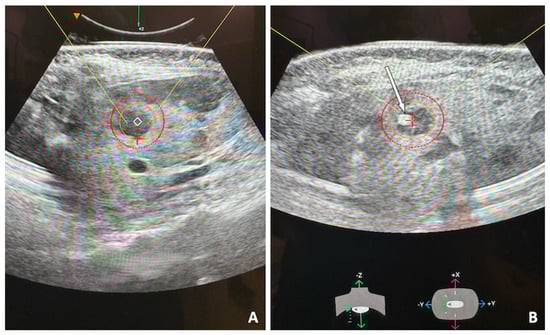

- Vidal-Jove, J.; Serres, X.; Vlaisavljevich, E.; Cannata, J.; Duryea, A.; Miller, R.; Merino, X.; Velat, M.; Kam, Y.; Bolduan, R.; et al. First-in-man histotripsy of hepatic tumors: The THERESA trial, a feasibility study. Int. J. Hyperth. 2022, 39, 1115–1123. [Google Scholar] [CrossRef]

- Wah, T.M.; Pech, M.; Thormann, M.; Serres, X.; Littler, P.; Stenberg, B.; Lenton, J.; Smith, J.; Wiggermann, P.; Planert, M.; et al. A Multi-centre, Single Arm, Non-randomized, Prospective European Trial to Evaluate the Safety and Efficacy of the HistoSonics System in the Treatment of Primary and Metastatic Liver Cancers (#HOPE4LIVER). Cardiovasc. Interv. Radiol. 2023, 46, 259–267. [Google Scholar] [CrossRef]

- Mendiratta-Lala, M.; Wiggermann, P.; Pech, M.; Serres-Créixams, X.; White, S.B.; Davis, C.; Ahmed, O.; Parikh, N.D.; Planert, M.; Thormann, M.; et al. The #HOPE4LIVER Single-Arm Pivotal Trial for Histotripsy of Primary and Metastatic Liver Tumors. Radiology 2024, 312, e233051. [Google Scholar] [CrossRef]